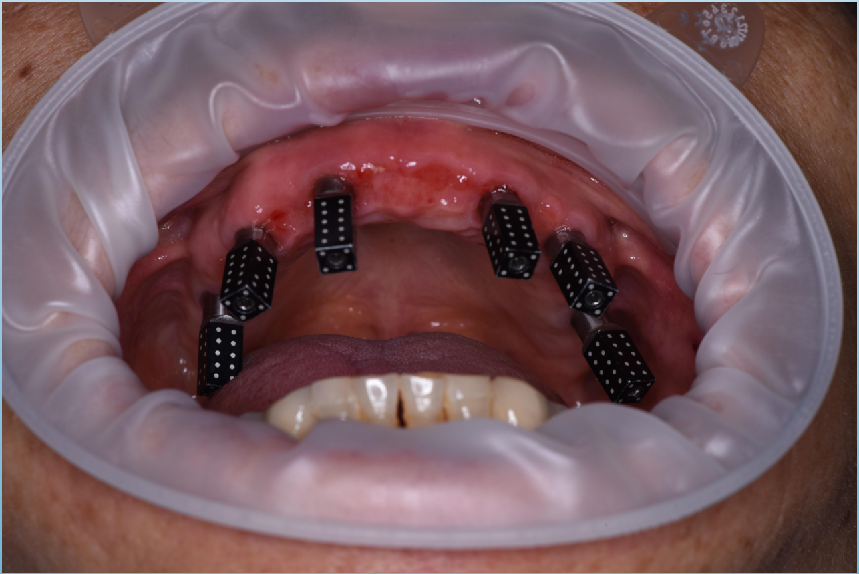

真实案例

TRUE CASE